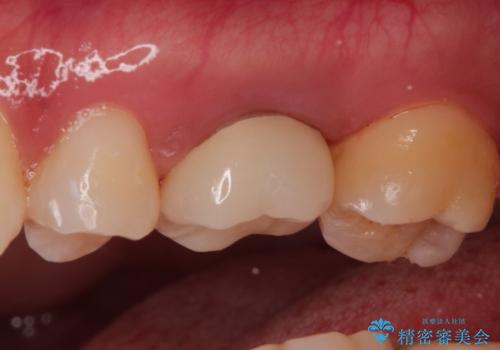

再根管治療後、歯周外科を行い、オールセラミッククラウンにて修復処置を行っております。

根管治療を行った大臼歯は速やかに被せ物の治療を行うことが必要です。